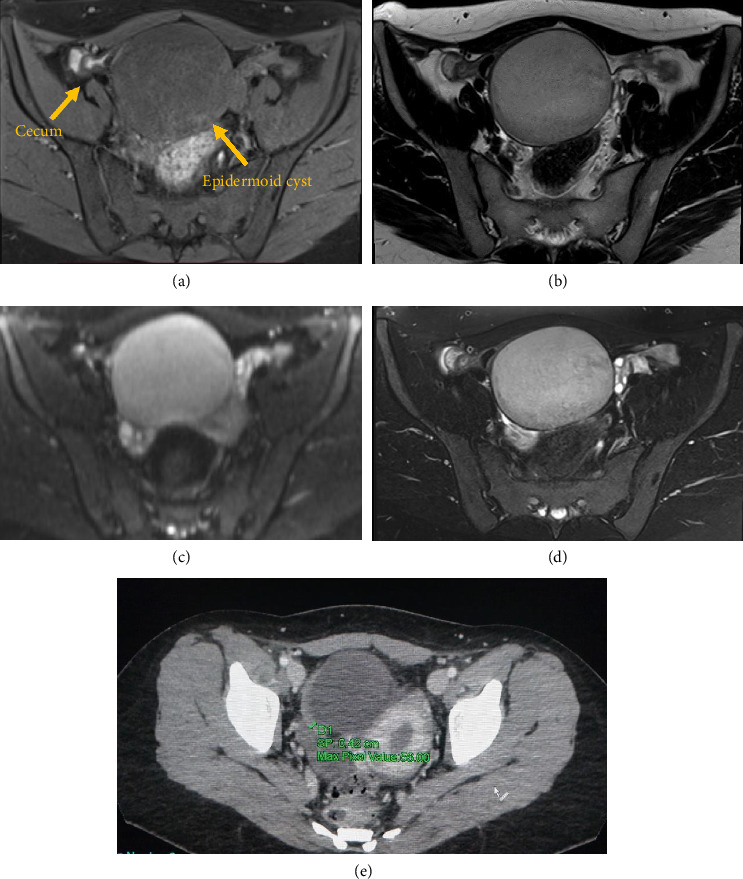

盲肠表皮样囊肿(CEC)是一种罕见的良性病变;起源可为获得性或先天性,但发病机制尚不清楚。我们提出一个病例报告,病人与盲肠囊肿治疗半结肠切除术。组织病理学显示盲肠表皮样囊肿(EC)。病例介绍:一名28岁女性因腹痛入院,无明显既往病史。行CT和MRI扫描,发现盆腔前部有一个大的囊性肿块。成像技术能够定位肿瘤的位置和大小;然而,他们并没有提供一个结论性的诊断。鉴别诊断为阑尾黏液囊肿、重复囊肿或子宫内膜异位囊肿形成。行腹腔镜右半结肠切除术;肿块未与周围脏器粘连。宏观表现为104 × 83 × 68 mm盲肠壁上的不规则腔外囊性病变。镜下,囊壁内衬角化层状鳞状上皮。未发现恶性肿瘤。因此,组织病理学评估导致最终诊断EC。结论:ECs是一种罕见的良性肿瘤,可以是后天的,也可以是先天性的。它们在临床和影像学表现上各不相同;病变可伴有非特异性症状或无症状。在性别分布和年龄上都有很大的异质性。影像技术是有用的,但最终的诊断只能在肿瘤完全手术切除和组织病理学检查后才能做出。

Introduction: Cecal epidermoid cyst (CEC) is a rare and benign lesion; the origin can be acquired or congenital, but the pathogenesis remains unclear. We present a case report of a patient with a cecal cyst treated by hemicolectomy. Histopathology revealed an epidermoid cyst (EC) of the cecum. Case Presentation: A 28-year-old woman was admitted to the hospital with abdominal pain, without significant past medical history. CT and MRI scans were performed, and a large cystic mass in the anterior portion of the pelvic region was detected. Imaging techniques managed to localize the site and dimensions of the neoplasm; however, they did not provide a conclusive diagnosis. The differential diagnosis was made with appendiceal mucocele, duplication cyst, or endometriotic cyst formation. Laparoscopic right hemicolectomy was performed; the mass did not present with any adhesions with the surrounding organs. Macroscopically, the mass appears as irregular extraluminal cystic lesion arising from the cecal wall of 104 × 83 × 68 mm. Microscopically, the cystic wall was lined by keratinized stratified squamous epithelium. No malignant findings were identified. Thus, the histopathologic evaluation leads to the final diagnosis of EC. Conclusions: ECs are rare benign neoplasms that can be acquired or congenital. They can vary both in their clinical and imaging presentation; the lesion can be associated with nonspecific symptoms or be asymptomatic. A wide heterogeneity both in sex distribution and age is observed. Imaging techniques are useful, but the final diagnosis can be made only after the complete surgical excision of the neoplasm and its histopathological examination.